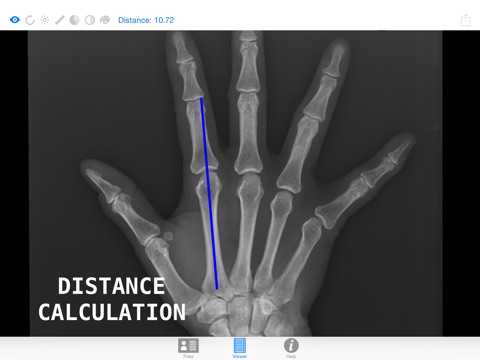

1. Check the length of your bones, or the area of some organs, isnt that cool? That information is stored in almost all DICOM files.